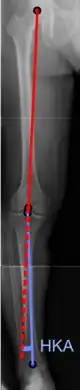

Radiography

On projectional radiography, the degree of varus or valgus deformity can be quantified by the hip-knee-ankle angle,[7] which is an angle between the femoral mechanical axis and the center of the ankle joint.[8] It is normally between 1.0° and 1.5° of varus in adults.[9] Normal ranges are different in children.[10]

Hip-knee-ankle angle